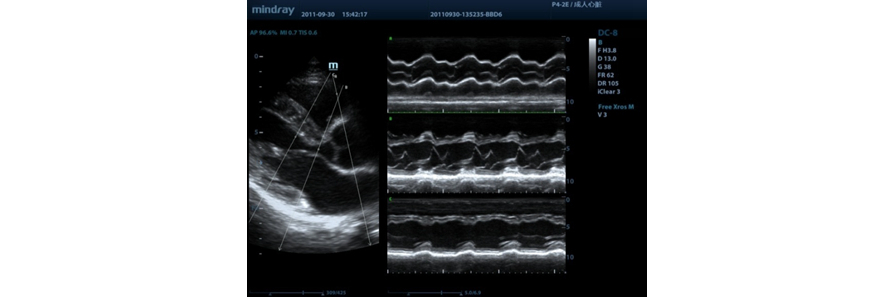

Free Xros M?

Dapatkan pengamatan anatomis akurat dengan penempatan baris sampel secara bebas pada sembarang sudut. Dapatkan gambar yang lebih baik melalui tampilan simultan hingga 3 baris sampel.